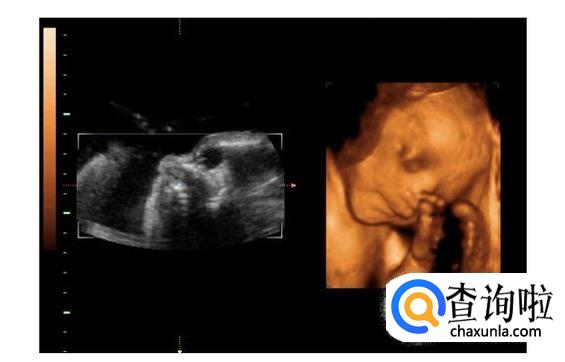

- 03

三维彩超就是将二维图像通过一个特殊的探头进行三维图像合成,透过屏幕可从各个方位观察胎宝宝。